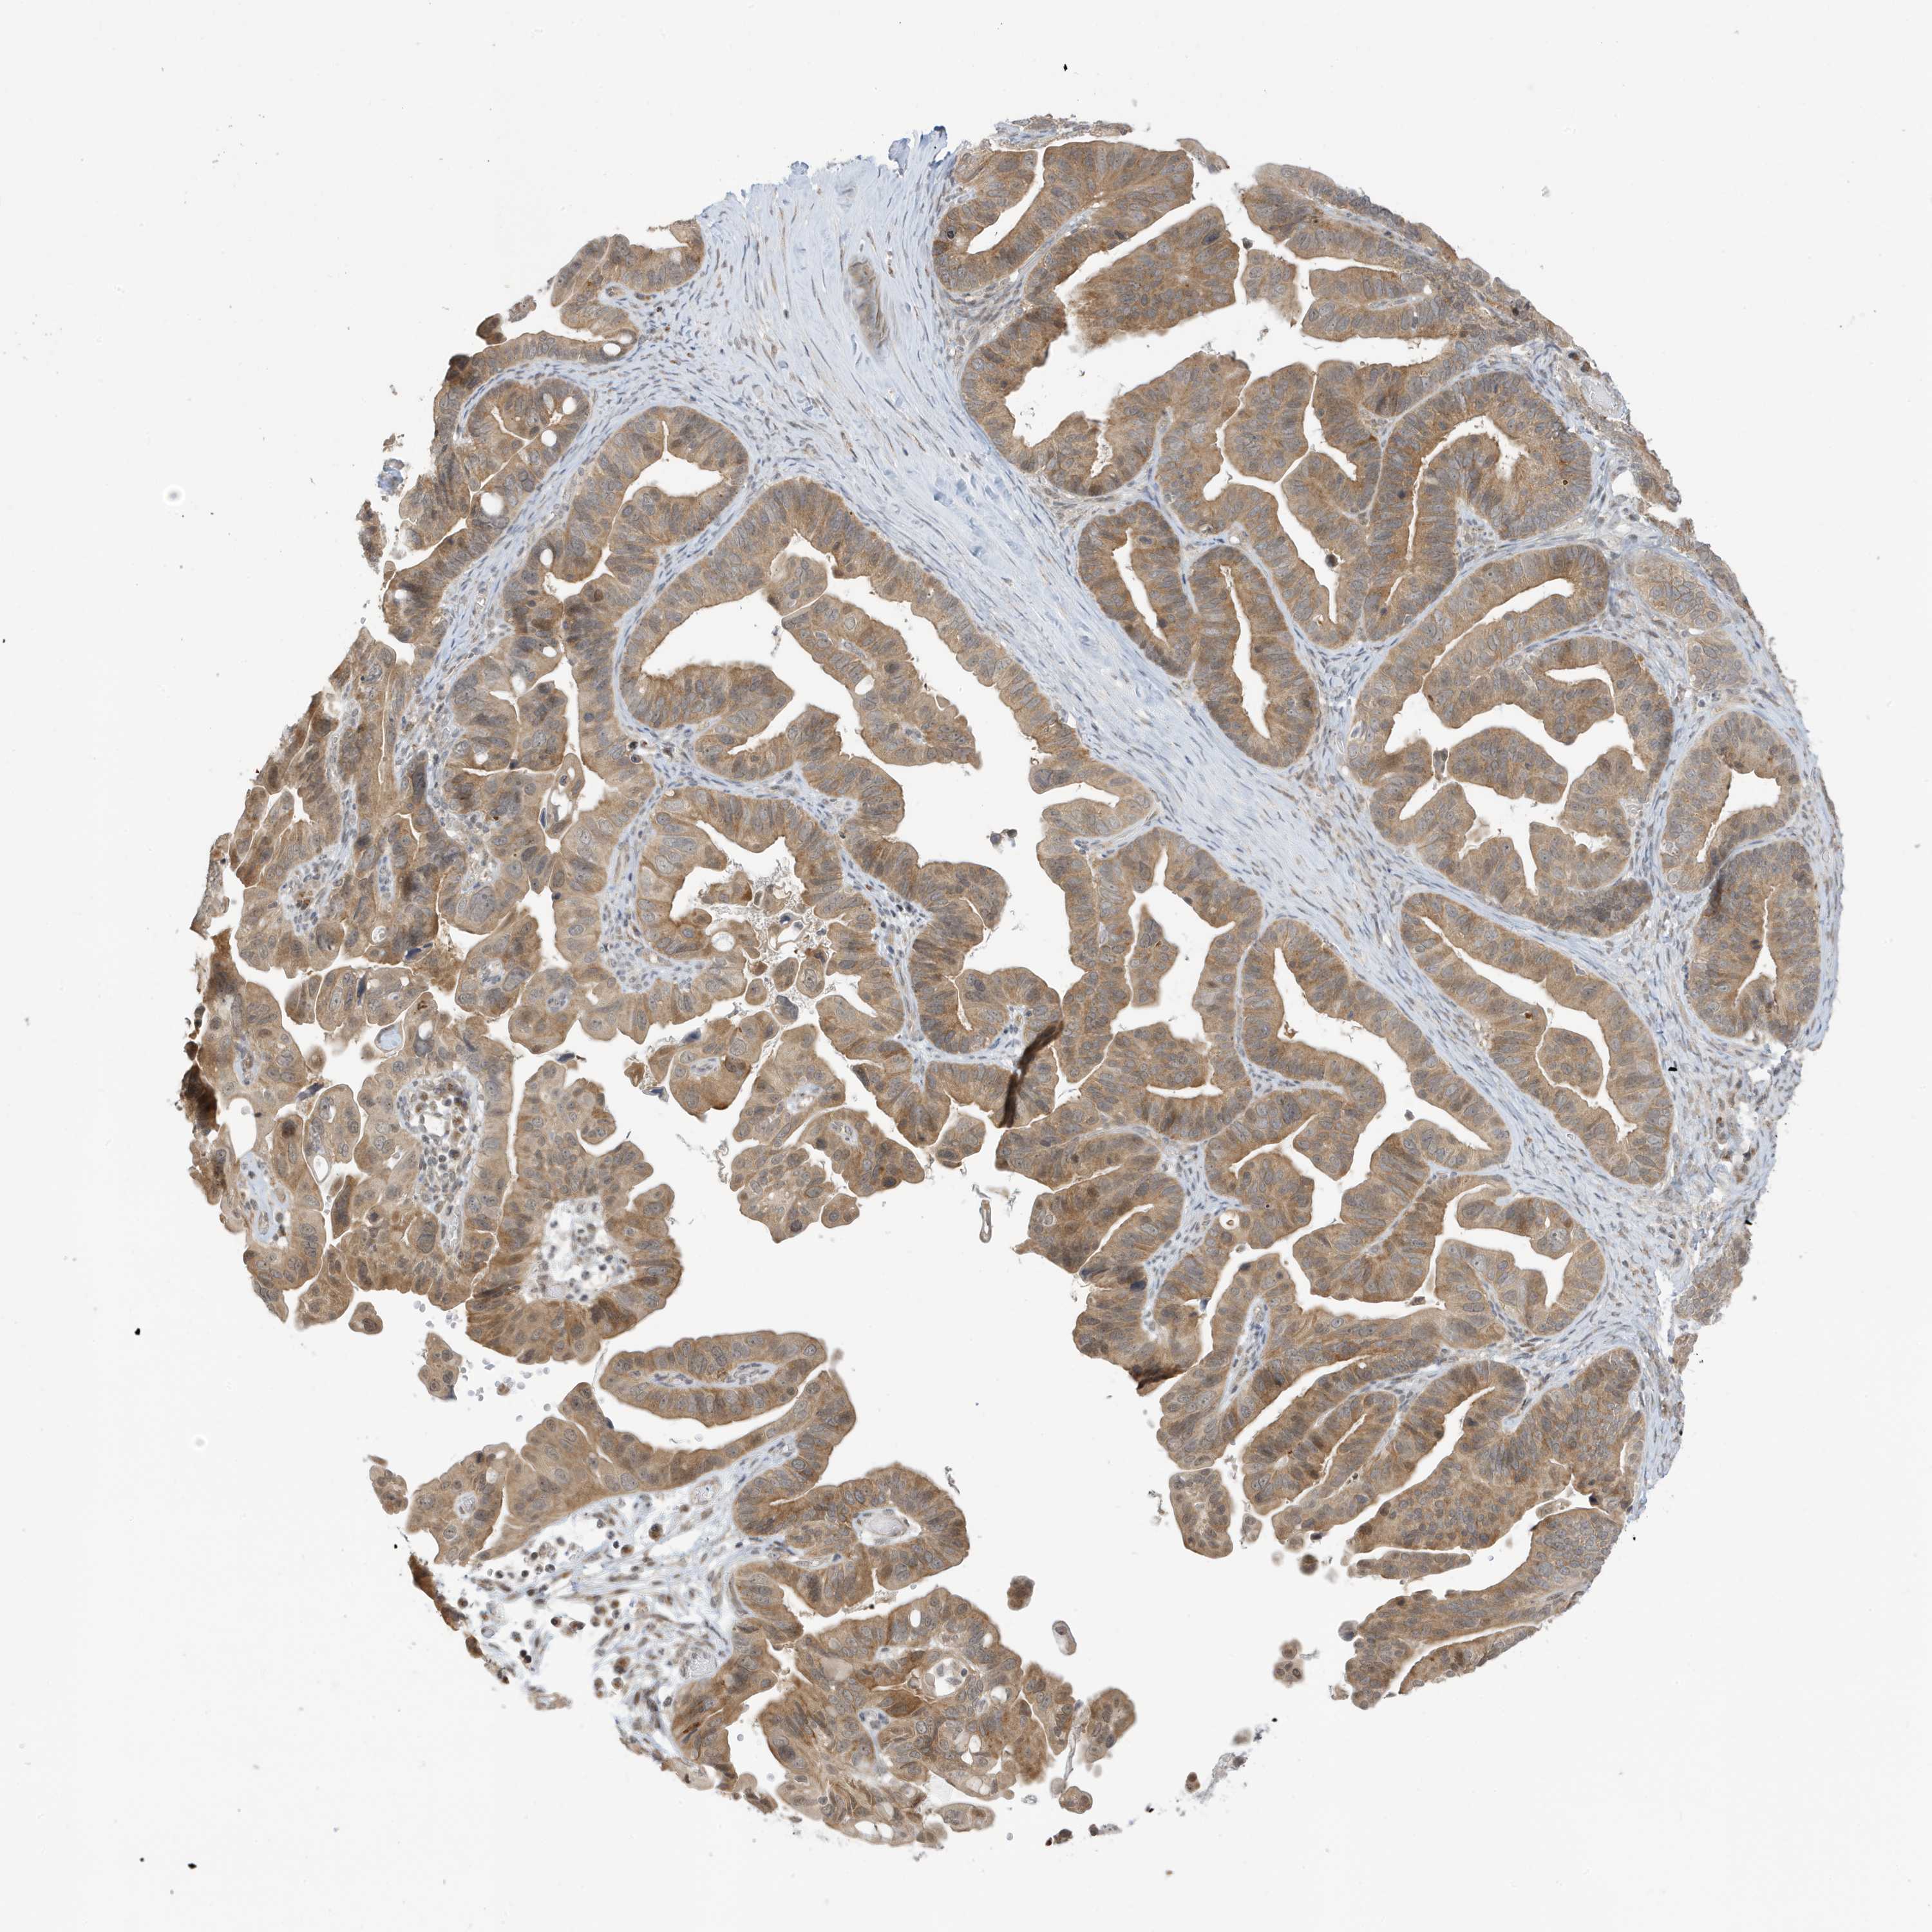

OVARIAN CANCER - Protein expressioni

A mouse-over function shows sample information and annotation data. Click on an image to view it in a full screen mode. Samples can be filtered based on level of antibody staining by selecting one or several of the following categories: high, medium, low and not detected. The assay and annotation is described here.

Note that samples used for immunohistochemistry by the Human Protein Atlas do not correspond to samples in the TCGA dataset.

Antibody stainingi

Antibody staining in the annotated cell types in the current human tissue is reported as not detected, low, medium, or high, based on conventional immunohistochemistry profiling in selected tissues. This score is based on the combination of the staining intensity and fraction of stained cells.

Each image is clickable and will lead to virtual microscopy that enables deeper exploration of all samples and also displays staining intensity scores, fraction scores and subcellular localization as well as patient and tissue information for each sample.

Antibody HPA034980

Antibody HPA034981

Carcinoma, endometroid